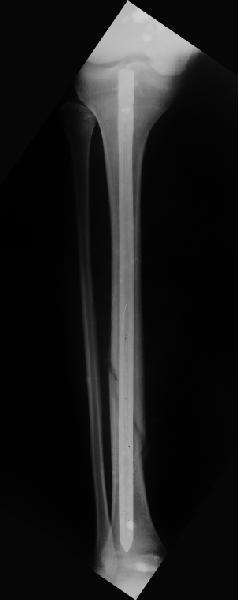

Вчера первый раз синтезировали голень гвоздем Fixion.

Спиральный оскольчатый перелом, ниже середины, у молодого парня. Сделали "классический" вариант гвоздя, который еще без винтов. Получилось все легко. Не торопясь, сделали операцию минут за 20. См. фото.

В отношении ранней нагрузки при спиральных переломах лучше не торопиться. По данному случаю необходимо достигнуть исчезновения щели между штифтом и внутреним кортексом по Rg. А так картинка прекрасная - и длина сегмента и репозиция. Можно поздравить, коллега!